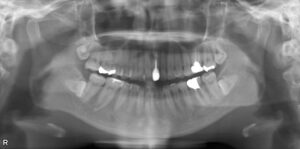

下顎大臼歯1本欠損症例

BEFORE AFTER 30歳女性/下顎1本欠損/インプラント埋込手術 【治療内容】 2年ほど前に他院でむし歯の治療を…